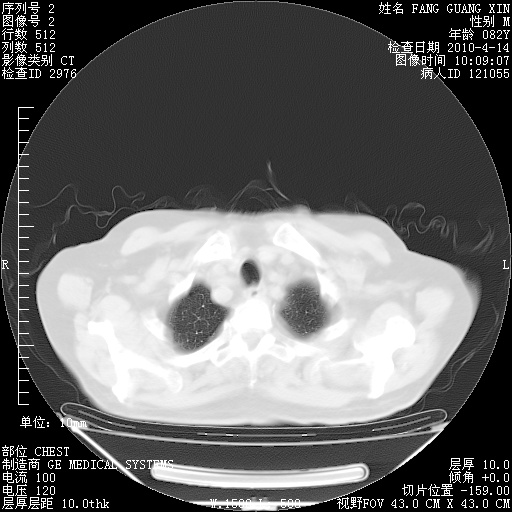

4月14日肺部CT

肺部CT平扫未见异常。